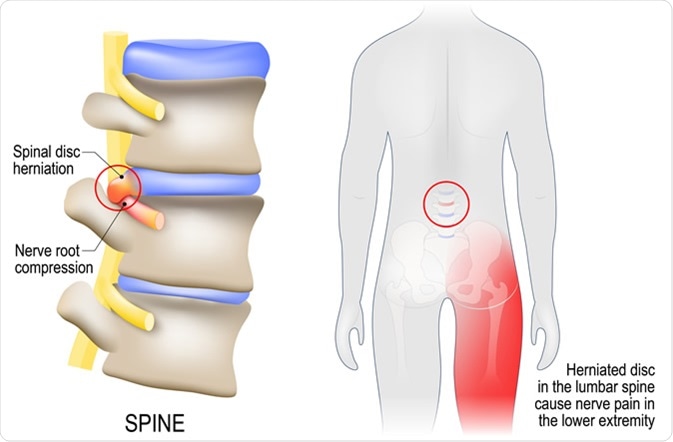

Sciatica

Sciatica refers to the pain that radiates along the path of the sciatic nerve. The sciatic nerve is the longest nerve in the body, running from the hips to the feet. When the nerve is pressed or irritated, it can lead to pain. The pain radiates from the lower lumbar spine to the buttock and down the back of the leg. The pain can be moderate to severe, accompanied by tingling, weakness, and numbness on the affected leg. Severe sciatica can be debilitating, preventing movement.

Sciatica diagram with vertebrae, disks and nerves - Image Credit: Designua / Shutterstock